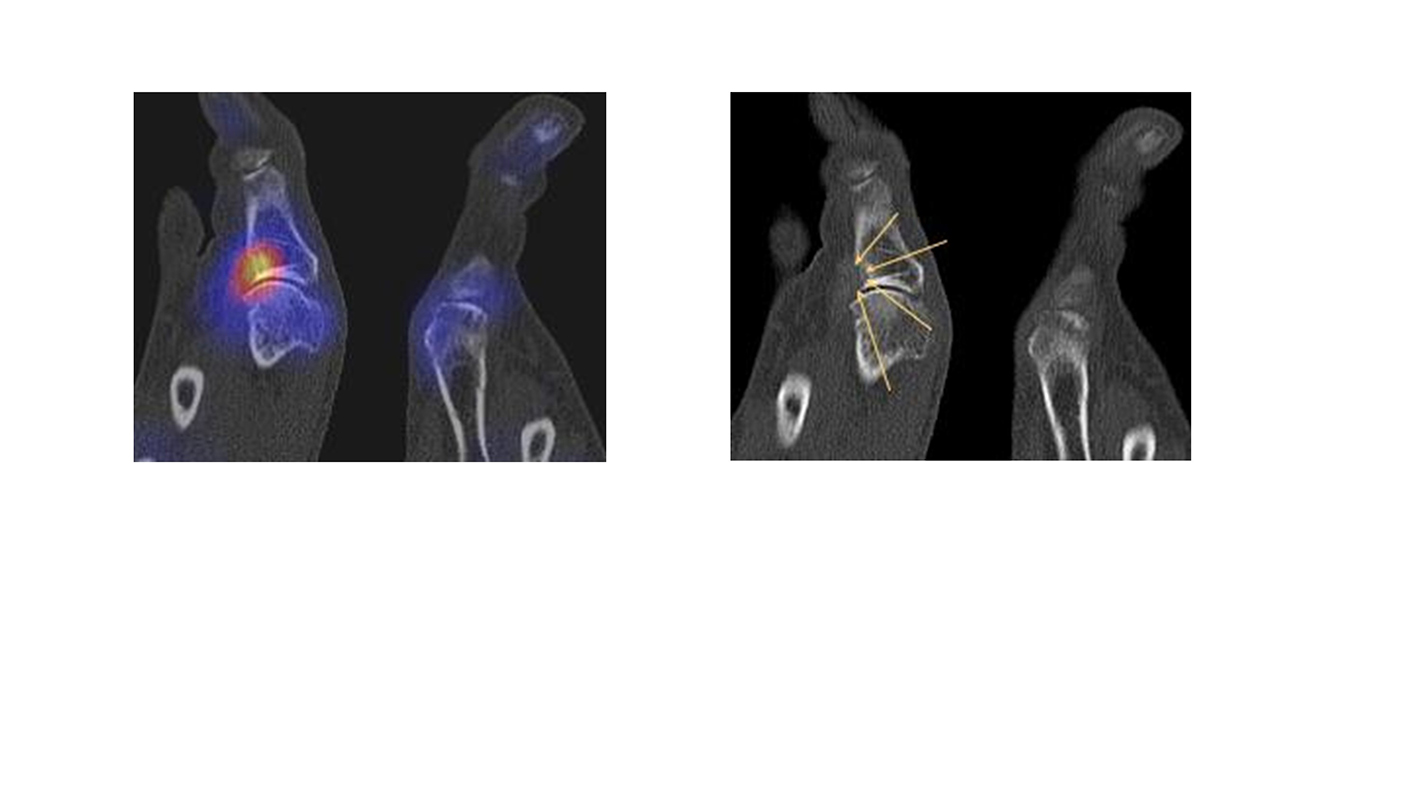

Abbildung 8.2. zeigt den Fall eines Patienten mit Verdacht auf ein knöchernes posteriores Impingement. Es bestanden Beschwerden dorsal bei Plantarflexion und ein Z. n. Distorsion des linken OSG vor 2,5 Jahren. Im MRT 2 Monate vor der SPECT/CT keine wegweisenden Befunde. Im SPECT/CT eindeutige fokal deutliche Mehrspeicherung im Bereich des Processus posterior tali.

Abbildung 8.3.a bis d demonstrieren Bilder einer Patientin mit Z. n. Arthrodese des linken OSG vor 6 Jahren. Das MRT ist bei ausgedehnten Metallartefakten nur bedingt aussagekräftig und weist nicht auf die auffälligen Befunde im SPECT/CT hin. Es bestehen sowohl fokale Stressreaktionen im Bereich eines Os trigonum und lateral im USG.

Abbildung 8.4.a bis d: Bilder einer Patientin mit chronischen Schmerzen im lateralen unteren Sprunggelenk links. Im MRT V. a. akzessorisches Knochenelement. Anamnestisch Beschwerden im Bereich des linken Sprunggelenkes seit 5 Monaten. Zuvor intensive sportliche Betätigung. Unter anderem tägliche atypische Belastung beider Füße durch Hinknien im Rahmen der Tätigkeit als Erzieherin. Diese Patientin hat nebenbefundlich bilaterale Akzessoria bzw. einen beiderseits angelegten Talus secundarius, der linksseitig jedoch nicht für die Symptomatik verantwortlich ist (die Bilder davon werden in Abbildung 3.5. gezeigt). Verantwortlich für die Symptomatik ist ein links posterolateral am Talus atypisches Knochenelement in einer Mulde mit engem Bezug zum unteren Sprunggelenk, DD atypisches laterales Os trigonum oder DD atypische Osteochondrosis dissecans. Die MRT konnte nicht differenzieren, wo die Schmerzursache genau lag. Im SPECT/CT (Abbildung 8.4.b und d) eindeutig fokale Mehrspeicherung im Bereich des atypischen Knochenelementes. Intraoperativ bestand der Aspekt einer Osteochondrosis dissecans.